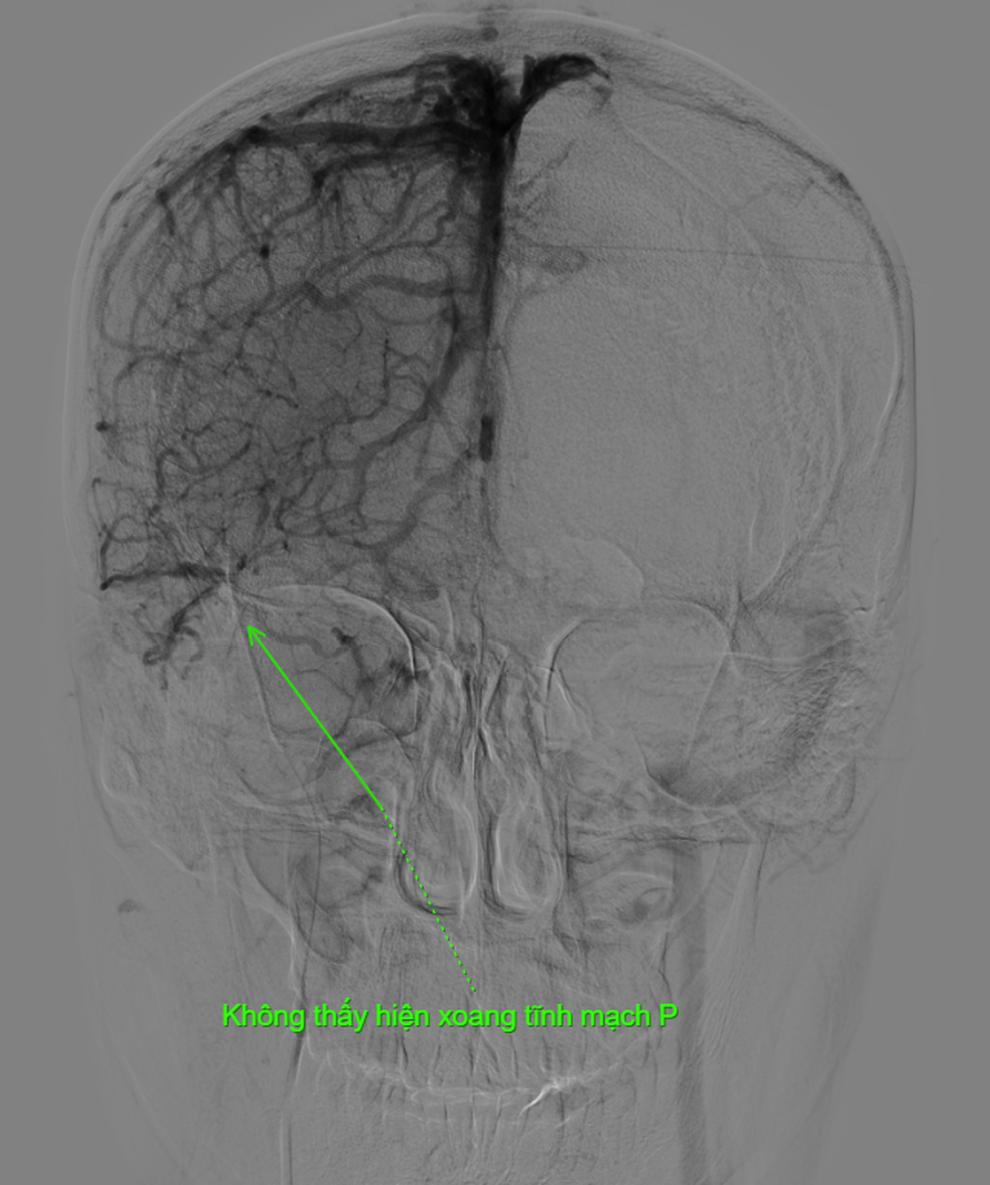

Chiều 3/12, BSCKII Nguyễn Văn Tiến, Trưởng khoa Ngoại Phụ khoa, Bệnh viện Ung bướu TPHCM, cho biết ông cùng các cộng sự vừa phẫu thuật cho một bệnh nhân mang khối u khổng lồ, khiến bụng to như ễnh ương.Bệnh nhân là cô gái 20 tuổi tên B. (ngụ TPHCM), sinh viên đại học năm thứ 3. Theo bệnh sử, cách đây gần 1 năm cô thấy bụng to dần, đến 6 tháng nay thì tốc độ gia tăng kích thước nhanh hơn.Một phần tưởng mình mập (bệnh nhân nặng gần 80kg), phần mặc cảm vì sợ bị cười chê và hiểu lầm, bệnh nhân che g...